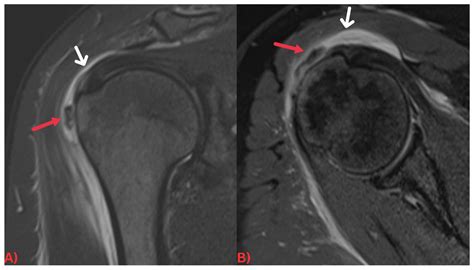

• Imaging Studies: X-rays, ultrasound, and magnetic resonance imaging (MRI) can help identify the presence of hydroxyapatite crystals and assess the extent of the deposits.

Imaging studies are particularly important in diagnosing HADD. X-rays can show calcifications in the affected areas, while ultrasound and MRI provide more detailed images of the soft tissues and joints. Laboratory tests can help rule out other conditions that may cause similar symptoms.